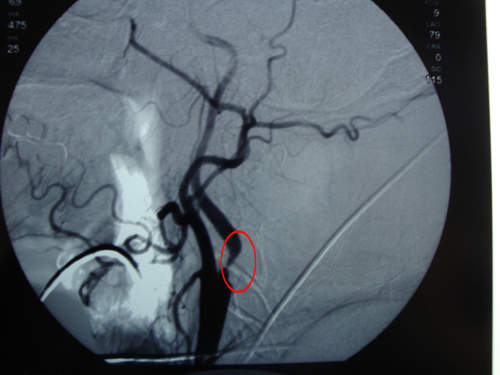

颈部血管彩超:双侧颈内动脉不均匀增厚伴斑块形成,左侧颈内动脉狭窄(70%-99%),右侧锁骨下动脉斑块形成,左侧椎动脉血流速度减低。

该患者为一例典型的左侧颈动脉狭窄伴对称肢体TIA症状发作,是CEA手术的经典指标。经会诊,于2010年7月31日由协作组张勤奕教授和宁新宇教授为其顺利实施了左侧颈内动脉内膜剥脱术。